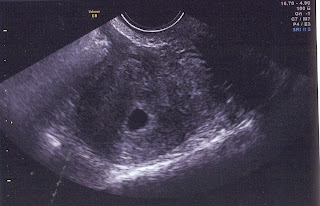

Todays scan shows a clear single gestational sac and we hope and pray that our singleton baby is strong, comfortable and ready to develop a heartbeat in time for next week's scan!!!!!!